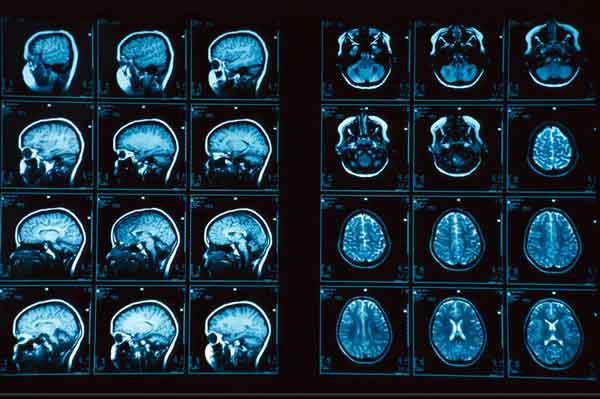

Gli autori hanno analizzato circa 160 studi sugli effetti comportamentali della psicochirurgia, ricerche di risonanza magnetica funzionale e analisi comportamentale di pazienti con lesioni cerebrali o con malattie psichiatriche per proporre un modello biologico di comportamento morale umano. “Il nostro obiettivo – spiega Fumagalli – era quello di individuare le strutture del cervello che regolano il nostro comportamento morale e di capire che cosa accade quando tale comportamento è alterato da una lesione cerebrale”.(AdnKronos)